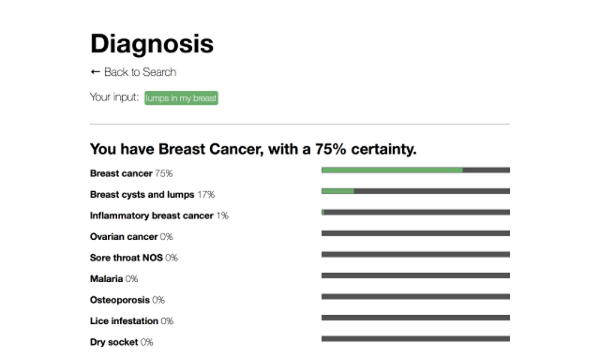

alexaMD

Provides a diagnosis based on symptoms trained on Mayo Clinic articles